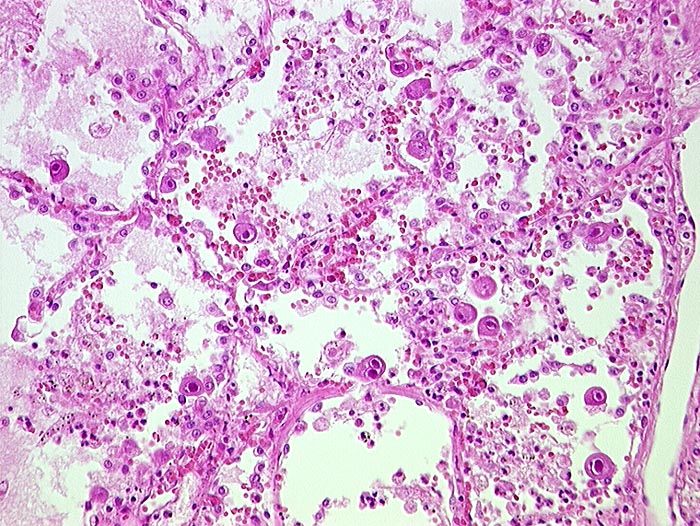

AP/ Cytomegalievirus-Infekt der Lunge

Cytomegalievirus-Infekt der Lunge

Entzündung infektiös

Lunge